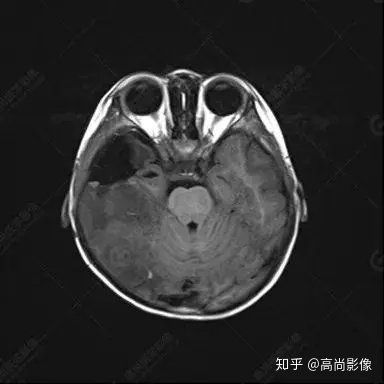

右側(cè)顳葉腫瘤切除術(shù)后(具體不詳):右側(cè)顳部骨質(zhì)不連續(xù)呈術(shù)后改變,右側(cè)顳葉術(shù)區(qū)見片狀長T1長T2信號(hào)影,F(xiàn)LAIR呈低信號(hào);術(shù)區(qū)后方右側(cè)顳枕葉見一巨大占位性病變影,邊界欠清,大小約6.2×5.8×4.3cm(前后×左右×上下),信號(hào)不均勻,T1WI呈等稍低信號(hào)間雜少許高信號(hào),T2WI呈高稍低混雜信號(hào),DWI示部分病灶彌散受限,相應(yīng)ADC圖減低,磁敏感序列見部分呈極低信號(hào),增強(qiáng)掃描可見明顯不均勻強(qiáng)化,鄰近硬腦膜及小腦幕增厚并明顯強(qiáng)化;另延髓右前方及右側(cè)橋小腦角區(qū)見一不規(guī)則形異常信號(hào)影,大小約3.2×1.3×3.7cm(左右×前后×上下),呈長T1稍長T2信號(hào),F(xiàn)LAIR呈等信號(hào),DWI未見受限,增強(qiáng)后明顯均勻強(qiáng)化,鄰近腦膜明顯強(qiáng)化。鄰近腦實(shí)質(zhì)及右側(cè)顳角明顯受壓;左側(cè)大腦半球未見局灶性信號(hào)異常,中線結(jié)構(gòu)稍左移。

右側(cè)顳葉腫瘤切除術(shù)后:現(xiàn)術(shù)區(qū)后方右側(cè)顳枕葉及延髓右前方占位,右側(cè)顳枕部硬腦膜及小腦幕明顯強(qiáng)化,結(jié)合既往影像資料,考慮為胚胎源性惡性腫瘤,如非典型畸胎樣/橫紋肌樣瘤(AT/RT)或原始神經(jīng)外胚層腫瘤(PNET)。